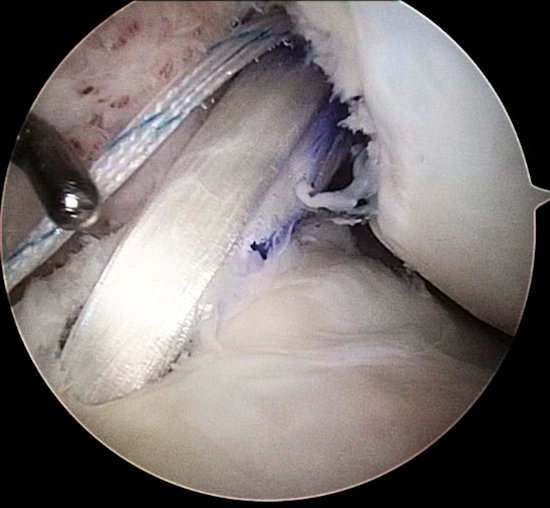

Kısmi ön çapraz bağ yaralanmalarında, bağ artıkları korunarak onarım

Ön çapraz bağ yaralanmalarının çoğunda bağın tamamı yapıştığı yerden kopar. Bu durumlarda, bağdan arta kalan dokuların faydası yoktur ve bağ cerrahisi sırasında çıkartılıp yeni bir bağ yapılır. Buna karşın, bazı yaralanmalarda ön çapraz bağın bazı lifleri korunmuştur; bağın iki kemik yapışma yeri arasında devamlılığı olan ve kısmen de olsa görev yapabilecek lifler vardır. Bu duruma kısmi ön çapraz bağ yaralanması denir.